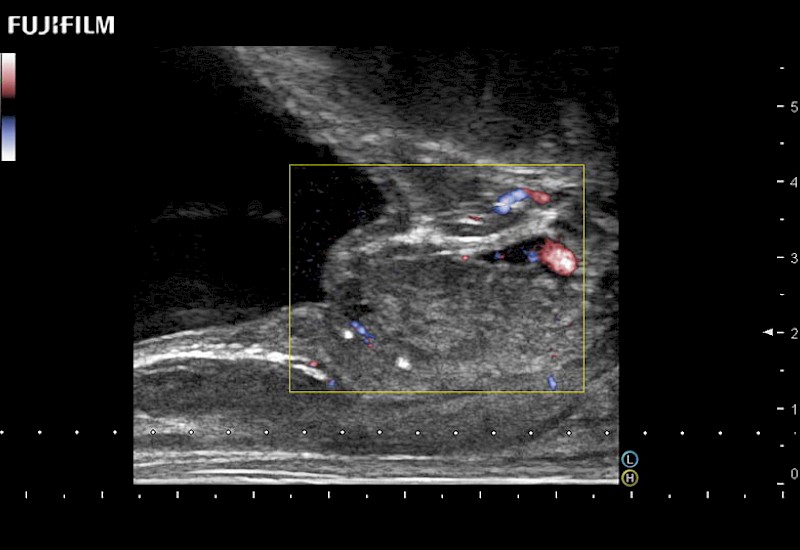

including: B-Mode, Color Doppler, Power Doppler, Fine Flow

– better visualization of tumors to improve understanding of blood flow information